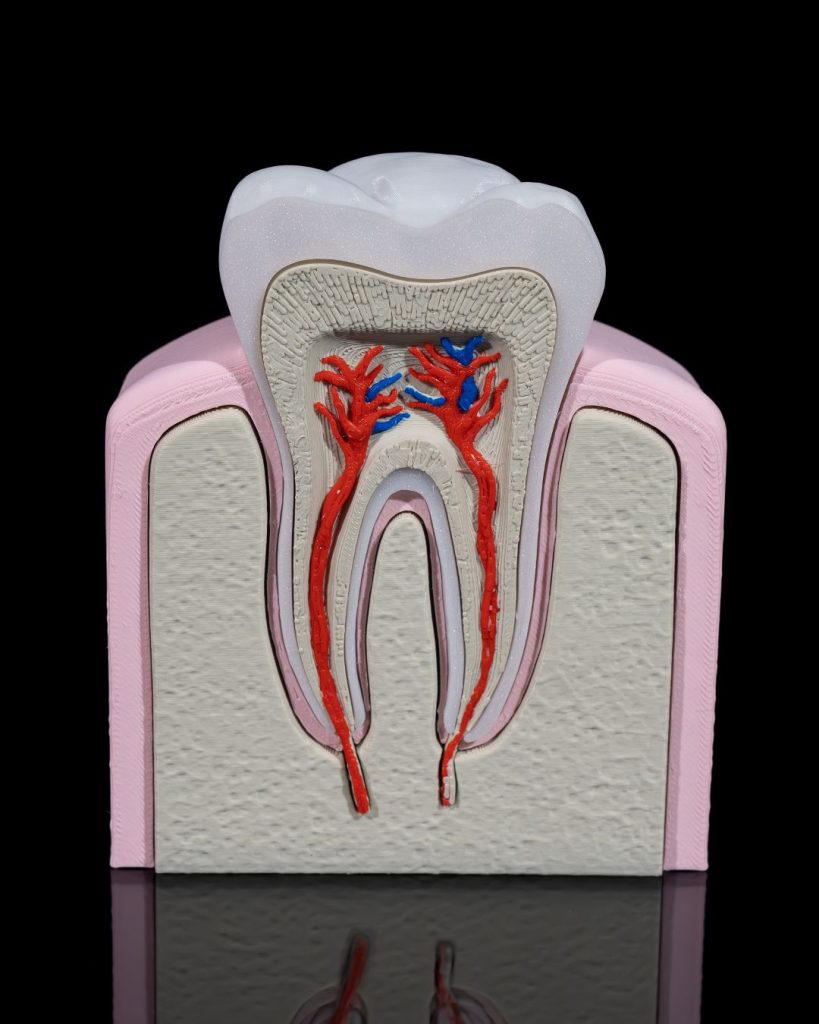

Human Tooth Anatomical Model

Example Short Description.

- Articulated and flexible for fun and display

- Intricately detailed to use

- Perfect as decor, a desk companion, or a thoughtful gift